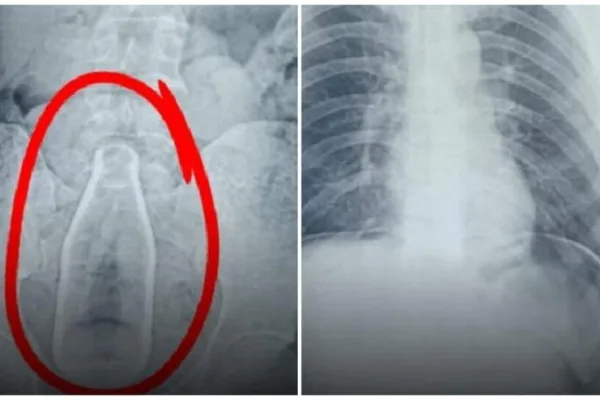

Pudukottai: மாற்று திறனாளி வயிற்றில் கண்ணாடி பாட்டில் அதிர்ந்த மருத்துவர்கள்!

சுமார் 2 மணி நேரம் நடந்த சிகிச்சைக்கு பின்னர் மாற்று திறனாளி வயிற்றில் இருந்த பாட்டில் வெளியே எடுக்கப்பட்டது. அப்போது விவசாயி வயிற்றில் இருந்த பாட்டில் செவன் …